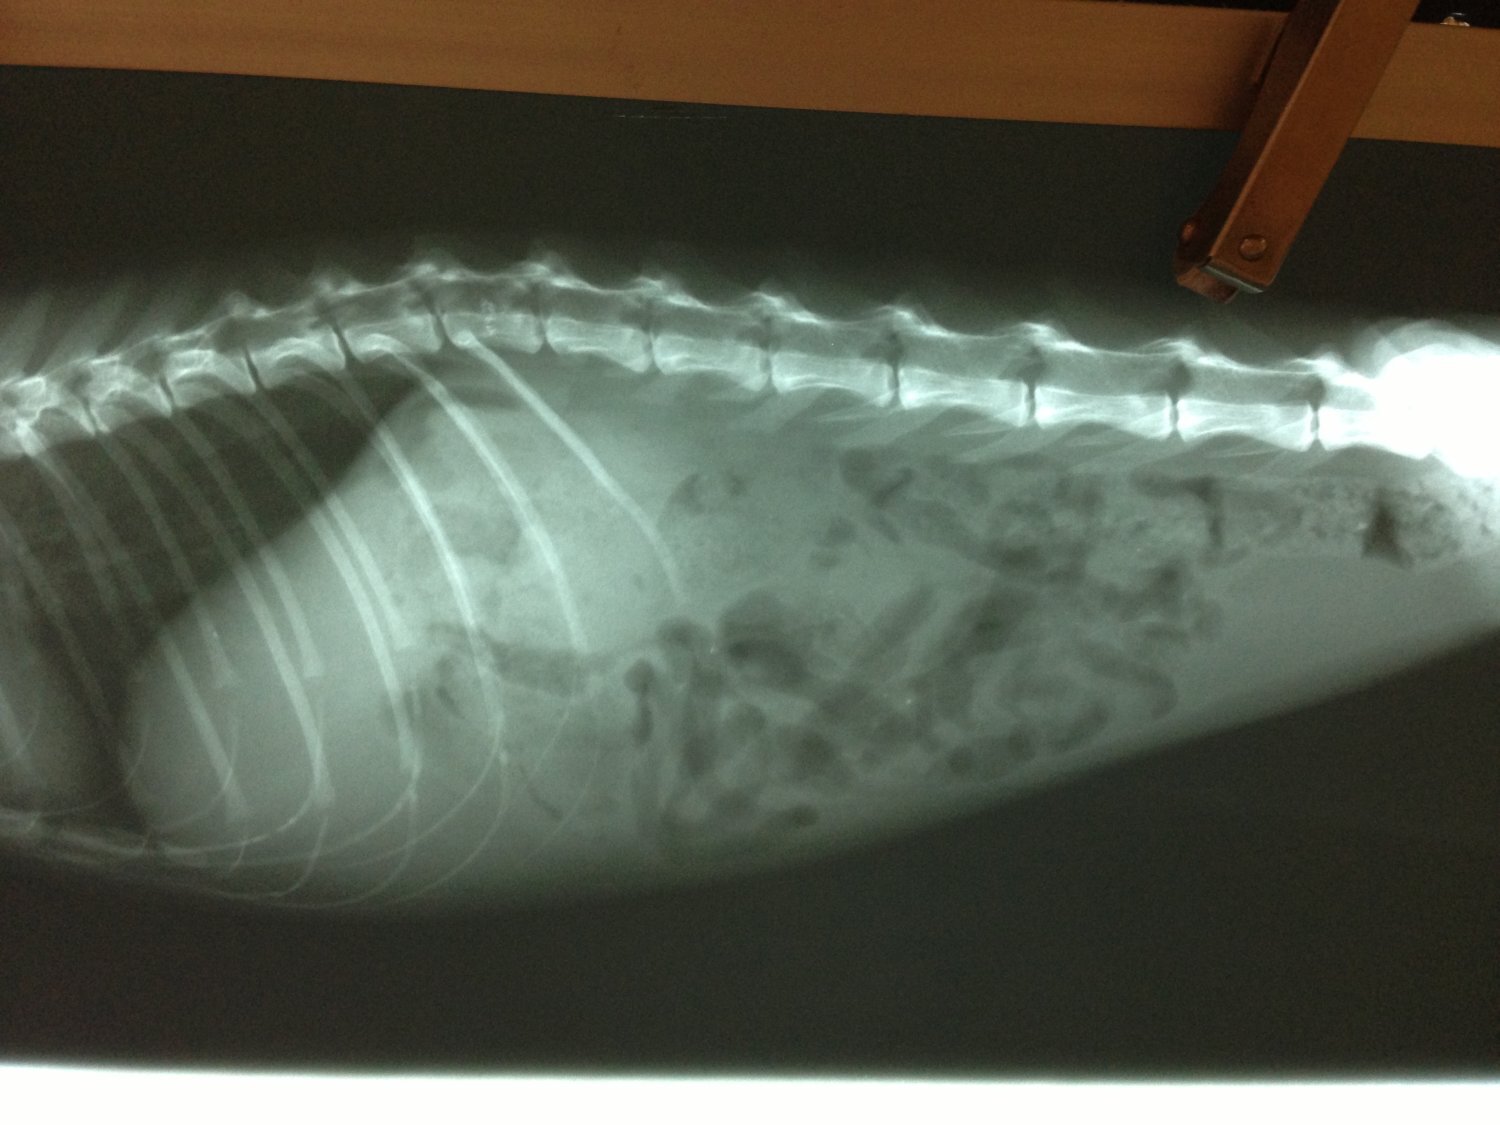

志工將貓帶走後,原本想說只要結紮,再放回原地生活,但這貓有些狀況,

非常的瘦,抽血檢查結果,白血球非常高,又貧血,但又無外傷,可能內部

有發炎感染,照X光顯示,腹部有奇怪的東西,也做血巴東蟲檢驗,但並無

驗出。